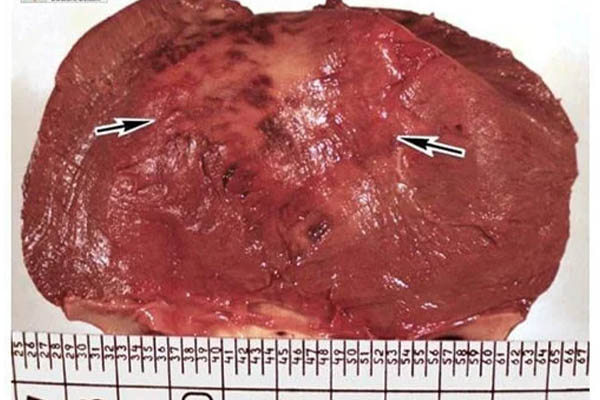

Saya ingin menunjukkan beberapa foto tentang apa yang terjadi pada sistem genitourinari dan organ dalam lainnya dari seorang pria ketika dia berhenti berhubungan seks.

Karena penyumbatan, timbunan kolesterol muncul di pembuluh darah, yang dapat membentuk gumpalan. Gumpalan adalah pertandanya hadirnya kemungkinan yang tinggi dari serangan jantung atau stroke. Itu adalah serangan jantung yang membunuh pria yang jantungnya bisa Anda lihat di foto.